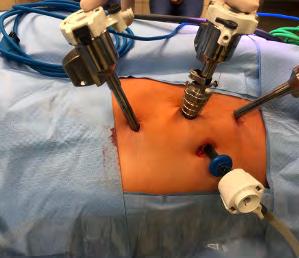

Souhrn: Úvod: Prezentujeme inovovaný postup operační léčby výrazně zvětšené prostaty způsobující retenci moči. Velmi dobré dlouhodobé výsledky transvezikální prostatektomie nás vedly k hledání méně invazivní alternativy. V řadě zemí s vyspělými zdravotnickými systémy se stále více prosazuje robotem asistovaná prostá prostatektomie pro benigní hyperplazii prostaty. K osvojení této metody nás vedl přehledný operační postup a výrazně zkrácená pooperační rekonvalescence. Prezentujeme provedení robotické enukleace na přístroji da Vinci Xi multiport, který jsme převzali ze zahraničí. Kazuistika: Muž, 61 let, ve výborném výkonnostním stavu, bez závažnějších komorbidit, měl výrazně zvětšenou prostatu o velikosti 7 × 6 × 5,5 cm s endovezikální prominencí, měl refrakterní retenci moči, a to i přes podávanou kombinovanou farmakoterapii v maximální dávce. Před operací byla provedena magnetická rezonance, která prokázala zvětšenou benigní hyperplazii prostaty bez suspekce na karcinom prostaty. Podobně i vyšetření per rectum i opakovaný odběr prostatického specifického antigenu byl bez podezření na přítomnost karcinomu. Pacientovi byla navržena operační léčba –robotem asistovaná enukleace zvětšené prostaty, se kterou souhlasil. Operace byla provedena na robotickém operačním systému da Vinci Xi multiport. Porty byly umístěny nad pupkem podobně jako u radikální prostatektomie. Pacient byl v Trendelendburgově poloze a operační přístup byl intraperitoneální. Močový měchýř byl otevřen ve vrcholu podélným řezem. Na okraje incize byly nasazeny dočasné fixační stehy pro dostatečný přístup pro robotické nástroje a kameru. Byla lokalizována ureterální ústí, která jsou často blízko ke zvětšené prostatě, a pak byla zahájena enukleace. Nejprve se nůžkami odstřihne celá vrstva sliznice močového měchýře a pak se provede enukleace bělavé hyperplazie prostaty od chirurgického pouzdra. Krvácení je promptně stavěno koagulací. U části operací je možné odstranit celou zvětšenou prostatu najednou, někdy je nezbytné odstranění po lalocích. Dalším krokem je stažení sliznice přes lůžko enukleace a její fixace pokračujícím stehem. Vhodné je použít ostnatý steh (například V-Loc nebo podobné). Nakonec se zavádí cévka a ta se ponechává na 5–7 dnů. Od června 2024 do září 2026 bylo provedeno 24 operací. Medián délky operace byl 145 (90–220) min a odhadované krevní ztráty byly 220 (100–800) ml. Medián hmotnosti enukleované prostaty byl 89 (57–142) g. Nezaznamenali jsme žádnou závažnou perioperační nebo ranou komplikaci.

Summary: Introduction: We present an innovative procedure for the surgical treatment of a significantly enlarged prostate causing urinary retention. The very good long-term results of transvesical prostatectomy led us to search for a less invasive surgical alternative. Robot-assisted simple prostatectomy for benign prostatic hyperplasia is increasingly promoted in many countries with advanced healthcare systems. The clear surgical procedure and significantly shortened postoperative recovery led us to adopt this method. We present the performance of robotic enucleation on the da Vinci Xi – multiport device, which we adopted from abroad. Case report: A 61-year-old man, with excellent performance status, without serious comorbidities, had a significantly enlarged prostate measuring 7 × 6 × 5.5 cm with endovesical prominence and had refractory urinary retention, despite the administered combination pharmacotherapy at maximum dose. A magnetic resonance imaging was performed before the operation, which demonstrated enlarged benign prostatic hyperplasia without suspicion of prostate cancer. Similarly, the rectal examination and repeated prostatic specific antigen collection were without suspicion of the presence of carcinoma. The patient was offered robot-assisted enucleation of the enlarged prostate, which he agreed to. The operation was performed with the da Vinci Xi multiport robotic operating system. The ports were placed above the umbilicus similarly to radical prostatectomy. The patient was in the Trendelenburg position and the surgical approach was intraperitoneal. The bladder was opened at the apex with a longitudinal incision and temporary fixation sutures were placed on the edges of the incision for sufficient access for robotic instruments and a camera. The ureteral orifices, which are often close to the enlarged prostate, were localized and then enucleation was initiated. First, the entire layer of the bladder mucosa is cut with scissors and then the whitish hyperplasia of the prostate is enucleated from the surgical capsule. Bleeding is promptly stopped by coagulation. In some operations, it is possible to remove the entire enlarged prostate at once, sometimes removal in lobes is necessary. The next step is to pull the mucosa over the enucleation site and fix it with a continuous suture. It is appropriate to use a barbed suture (for example, V-Loc or similar). Finally, a catheter is inserted and left in place for 5–7 days. From June 2024 to September 2026, 24 operations have been performed. The median duration of the operation was 145 (90–220) minutes and the estimated blood loss was 220 (100–800) mL. The median weight of enucleated prostate was 89 (57–142) g. We did not experience any serious perioperative or early complications. In three patients, a temporary indwelling catheter was required due to high post-void residual. After repeated catheter removal, urinary retention recurred in only one patient. In three patients, a bladder diverticulum was also resected together with the enucleation of the benign prostatic hyperplasia. Conclusion: Robotic enucleation is a suitable alternative to open surgery for a severely enlarged prostate, especially with a large middle lobe. The disadvantage is the higher cost of the operation. The advantages are enucleation under visual control, the possibility of rapid coagulation and covering the site with

Operace byly provedeny na robotickém operačním systému druhé generace da Vinci Si® do září 2016 (n=9), od července 2018 byly provedeny na novém systému čtvrté generace da Vinci Xi® (Intuitive Surgical, Inc.). Ve všech případech byl použit standardní multiportový přístup. Všechny operace byly provedeny transperitoneálně a vždy byla provedena pyeloplastika s přerušením močovodu dle Andersona a Hynese [2]. Resekce pánvičky byla zvolena dle míry dilatace pánvičky a anatomických poměrů zjištěných během operace. Výkony byly provedeny ve standardní poloze na boku se sklonem 45–60° (obr. 1). Kapnoperitoneum s tlakem 8 mmHg bylo založeno vždy otevřenou technikou dle Hassona, při níž je z malé laparotomie v medioklavikulární čáře asi 1–2 cm kraniálně od pupku vypreparován vstup pro kamerový port. U da Vinci Si® byl použit 12mm kamerový port, dva 8mm robotické troakary spolu s 12mm asistenčním portem. U da Vinci Xi® byly využity čtyři 8mm trokary a jeden 8mm asistenční port. U malých dětí do 10 let věku byly pro menší rozměry břicha použity pouze tři 8mm robotické troakary spolu s jedním 8mm asistenčním portem (obr. 2). K provedení anastomózy a uzavření pánvičky byly použity vstřebatelné monofilamentní stehy Monocryl® 6-0 nebo 5-0.